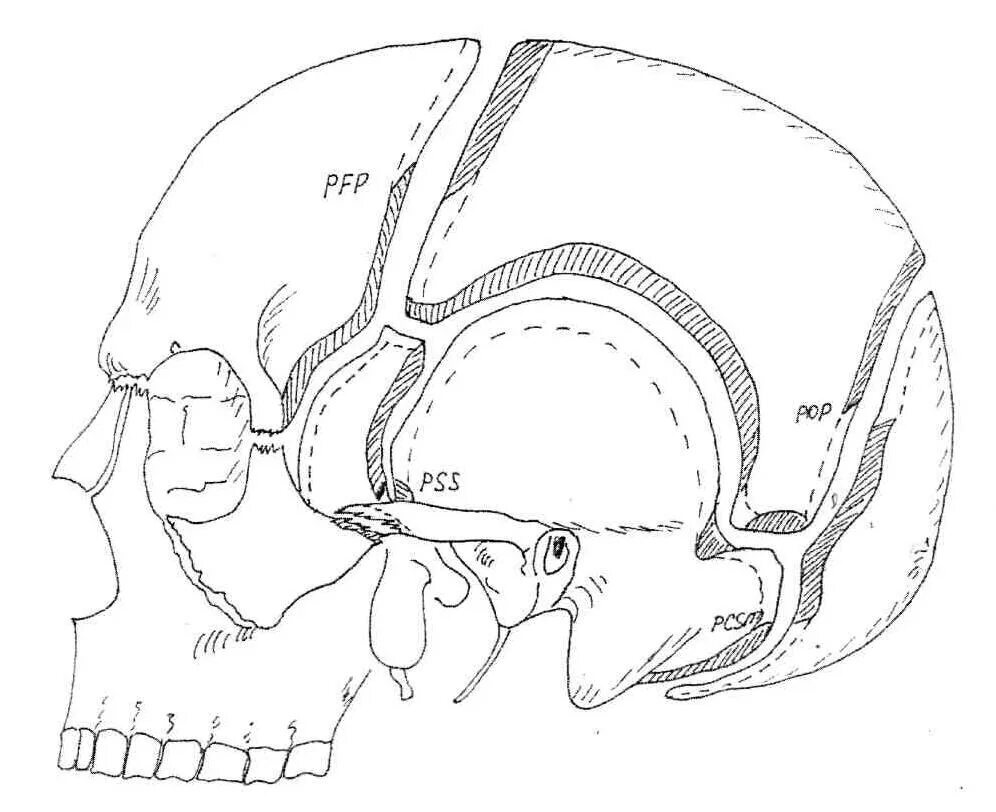

Остеопатия череп